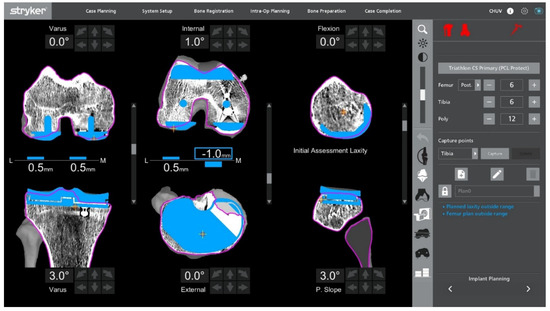

With the UKA components in place, an initial intraoperative functional alignment assessment is performed (Figure 3). The polyethylene insert is reinserted to enable a dynamic evaluation of ligament balance in both flexion and extension, providing essential data for potential plan adjustments. After registration and verification of reference points, this assessment is repeated through the full range of motion, allowing real-time adaptation to refine the 3D plan.

Figure 3.

Intraoperative ligament balance assessment after registration. The polyethylene insert is reinserted prior to implant removal to evaluate dynamic ligament balancing through flexion and extension.

Varus–valgus stress tests are applied at multiple flexion angles to assess ligament balance. The target is 1–2 mm of controlled laxity with symmetric medial and lateral gaps in extension and at 90° of flexion. The medial–lateral side-to-side difference should be ≤1 mm to maintain optimal soft-tissue tension and avoid mid-flexion instability.

2.6. Robotic Planning and Bone Resection

After confirming ligament balance, the preoperative plan is adjusted if necessary to optimize bone preservation and soft-tissue tension. Robotic-guided resections are performed according to the final plan (Figure 5). The intraoperative screen may display a plan with submillimetric residual gaps, which is an intended target and acceptable without stress testing at this stage. At 90° of flexion, a small sub-millimetric lateral laxity is acceptable and often desirable to permit a physiological medial-pivot pattern while maintaining coronal stability.

Figure 5.

Final adjusted implant positioning and robotic resection plan after gap assessment, intentionally showing sub-millimetric residual gaps at the no-stress stage. Planning aims optimize ligament balance while preserving bone.